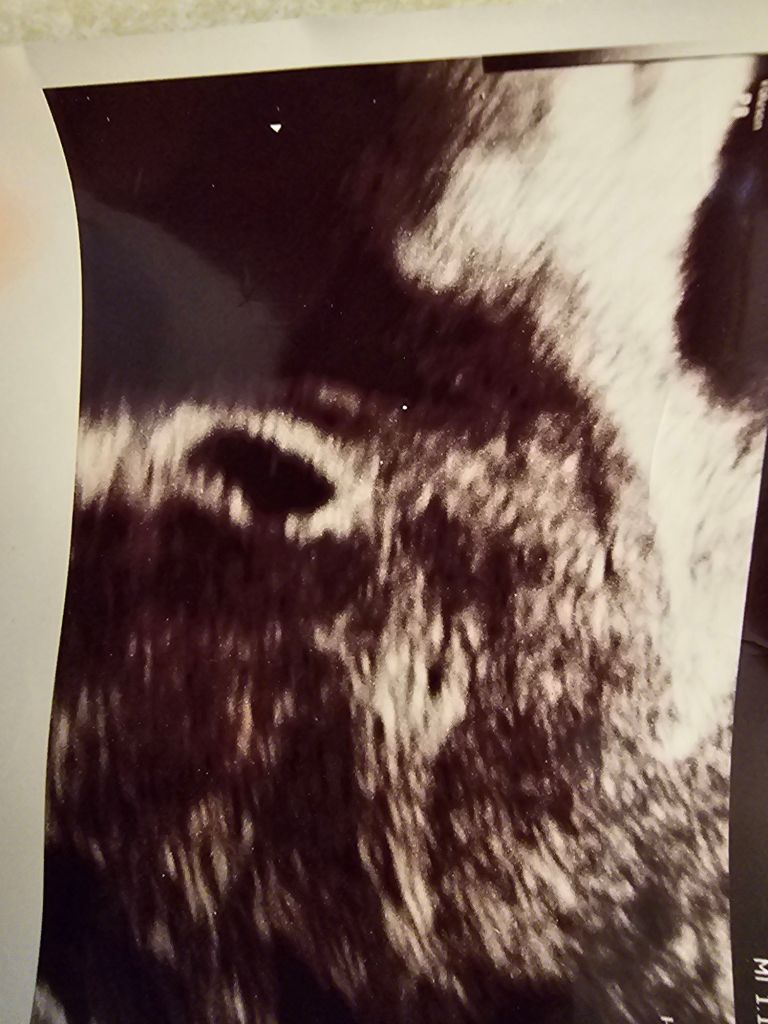

After this, we decided to just let things rest for a bit. Not to force things and let nature take its course. Then I missed my period! I called my doctor so excited and they even offered to see me early! My OB won’t see me until I’m 13 weeks, so I jumped at the chance to see this little bug.

They ran my bloodwork, and we waited. They wanted me to come in for an ultrasound because my HCG was a lot higher than expected at 4 weeks. It was more aligned to 7 weeks. When we got in there to take a look, they were having trouble finding the baby. We finally found it in my fallopian tube, and its little heartbeat was so strong… I lost it. I was given a choice to have them take the tube surgically or to have a chemically induced DNC. I opted for the drugs. We werent even 10 min away from the office when my OB called and told me that i needed surgery immediately as i was in danger of a rupture.